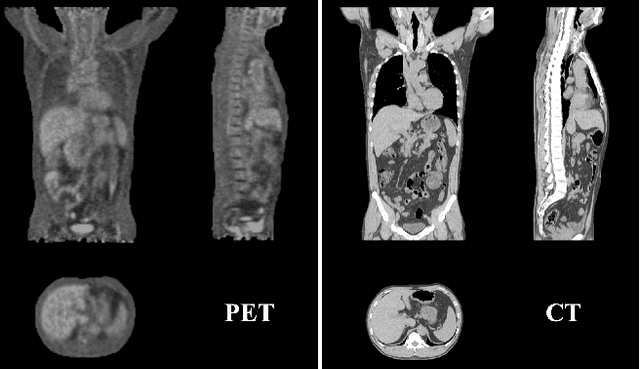

Abstract:Positron emission tomography (PET) is a cornerstone of modern oncologic and neurologic imaging, distinguished by its unique ability to illuminate dynamic metabolic processes that transcend the anatomical focus of traditional imaging technologies. Radiology reports are essential for clinical decision making, yet their manual creation is labor-intensive and time-consuming. Recent advancements of vision-language models (VLMs) have shown strong potential in medical applications, presenting a promising avenue for automating report generation. However, existing applications of VLMs in the medical domain have predominantly focused on structural imaging modalities, while the unique characteristics of molecular PET imaging have largely been overlooked. To bridge the gap, we introduce PET2Rep, a large-scale comprehensive benchmark for evaluation of general and medical VLMs for radiology report generation for PET images. PET2Rep stands out as the first dedicated dataset for PET report generation with metabolic information, uniquely capturing whole-body image-report pairs that cover dozens of organs to fill the critical gap in existing benchmarks and mirror real-world clinical comprehensiveness. In addition to widely recognized natural language generation metrics, we introduce a series of clinical efficiency metrics to evaluate the quality of radiotracer uptake pattern description in key organs in generated reports. We conduct a head-to-head comparison of 30 cutting-edge general-purpose and medical-specialized VLMs. The results show that the current state-of-the-art VLMs perform poorly on PET report generation task, falling considerably short of fulfilling practical needs. Moreover, we identify several key insufficiency that need to be addressed to advance the development in medical applications.

Abstract:Positron Emission Tomography (PET) imaging plays a crucial role in modern medical diagnostics by revealing the metabolic processes within a patient's body, which is essential for quantification of therapy response and monitoring treatment progress. However, the segmentation of PET images presents unique challenges due to their lower contrast and less distinct boundaries compared to other structural medical modalities. Recent developments in segmentation foundation models have shown superior versatility across diverse natural image segmentation tasks. Despite the efforts of medical adaptations, these works primarily focus on structural medical images with detailed physiological structural information and exhibit poor generalization ability when adapted to molecular PET imaging. In this paper, we collect and construct PETS-5k, the largest PET segmentation dataset to date, comprising 5,731 three-dimensional whole-body PET images and encompassing over 1.3M 2D images. Based on the established dataset, we develop SegAnyPET, a modality-specific 3D foundation model for universal promptable segmentation from PET images. To issue the challenge of discrepant annotation quality of PET images, we adopt a cross prompting confident learning (CPCL) strategy with an uncertainty-guided self-rectification process to robustly learn segmentation from high-quality labeled data and low-quality noisy labeled data. Experimental results demonstrate that SegAnyPET can correctly segment seen and unseen targets using only one or a few prompt points, outperforming state-of-the-art foundation models and task-specific fully supervised models with higher accuracy and strong generalization ability for universal segmentation. As the first foundation model for PET images, we believe that SegAnyPET will advance the applications to various downstream tasks for molecular imaging.